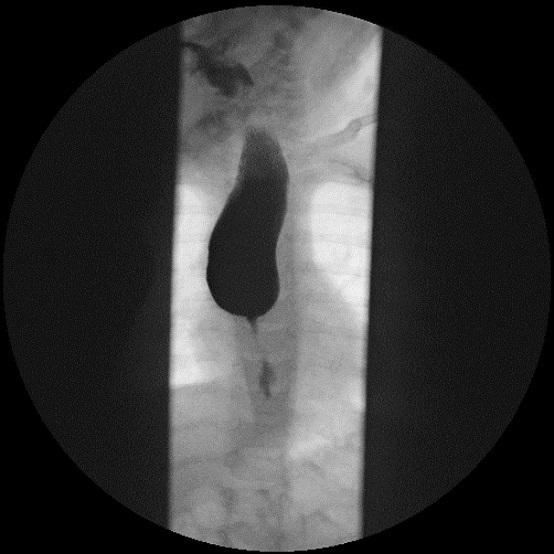

Como parte del estudio se realiza un estudio analítico y una ecografía abdominal, que no muestran alteraciones. Dada la persistencia del cuadro de vómitos, se decide realizar una endoscopia digestiva alta (Fig. 1) en la que se evidencia una estenosis esofágica que impide el paso del endoscopio. El tercio proximal del esófago se muestra dilatado, sin estrías ni anillos. Se completa estudio con tránsito digestivo superior (Fig. 2), donde se confirma estenosis esofágica en el tercio medio-distal, con escaso paso del contraste. En la anatomía patológica de la mucosa se observan cambios inflamatorios de características inespecíficas, sin metaplasia intestinal.

El esofagograma con contraste es la maniobra diagnóstica inicial, junto con la radiografía de tórax anteroposterior y lateral3. Generalmente muestra una dilatación proximal seguida de un área corta de estrechamiento concéntrico aperistáltico, con imposibilidad para el paso del contraste.